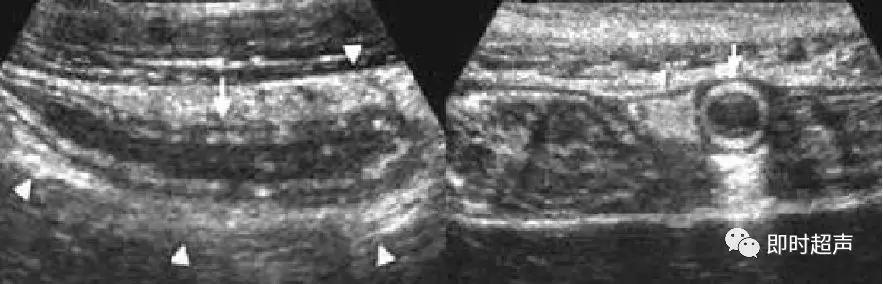

幽门肥厚狭窄声像图:

增厚的幽门肌层(三角箭头之间),增长的幽门管(长箭头之间)。

先天性肥厚性幽门狭窄

幽门纵切呈“宫颈征”。幽门横切面呈“靶环征”